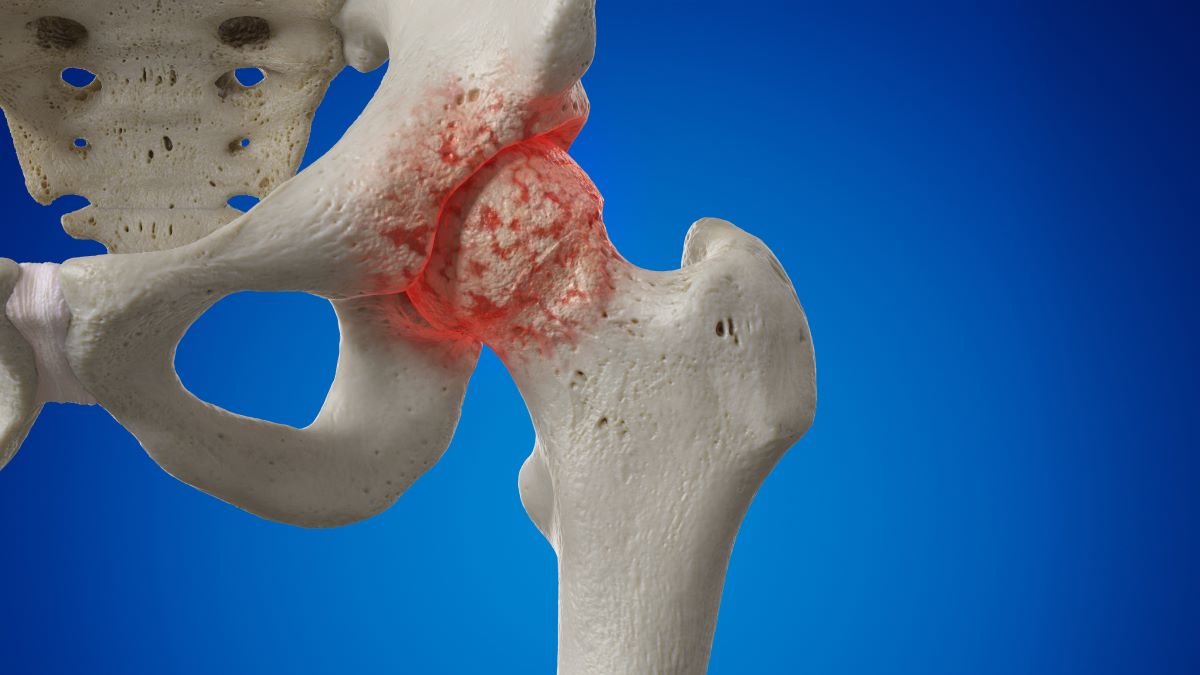

퇴행성 질환

퇴행성 질환은 시간이 지남에 따라 관절의 연골이 마모되어 통증을 유발하는 흔한 원인입니다.

- 관절염: 관절의 염증으로 인해 통증이 발생하며, 특히 나이가 많은 사람들에게서 흔히 발생합니다.

- 고관절 이형성증: 대개 어린 시절 발병하지만, 성장하면서 문제가 나타나 통증이 발생할 수 있습니다.

퇴행성 질환은 주로 나이와 관련이 있으며, 초기에는 경미한 통증으로 시작하지만 점진적으로 심각해질 수 있습니다. 이 때문에 조기 발견과 치료가 중요합니다.